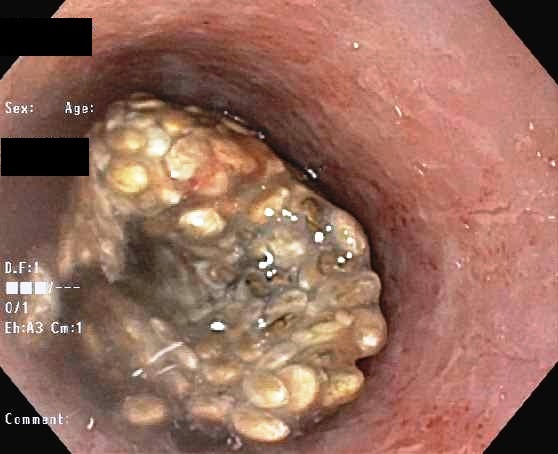

Ya en el nosocomio los médicos analizaron al sujeto y observaron un tapón del hidrogel, por lo que determinaron que estos granos pueden absorber hasta 27 veces su tamaño en agua, "por esta razón, pacientes con un historial de disfagia o estenosis esofágicas (estrachamiento de este órgano), deben de ser advertidos que las semillas de chía sólo se deben consumir cuando han tenido la capacidad de expandirse por completo en un líquido antes de la ingestión. Si el esófago se ve impactado con la chía, removerla será complicado por las herramientas tradicionales utilizadas para la extracción endoscópica", escribió Rebecca E. Rawl, doctora del Carolinas HealthCare System, en una nota de prensa.

La doctora explicó que para poder remover el bloqueo ninguna de las herramientas habituales logró el cometido, debido a que tenía una consistencia similar a la masa Play-Doh (dura pero a la vez suave) por lo que tuvieron que usar un endoscopio pequeño generalmente utilizado para bebés con el que rompió pequeños trozos de chía hasta que tuviera un tamaño suficiente para poder empujarlo.